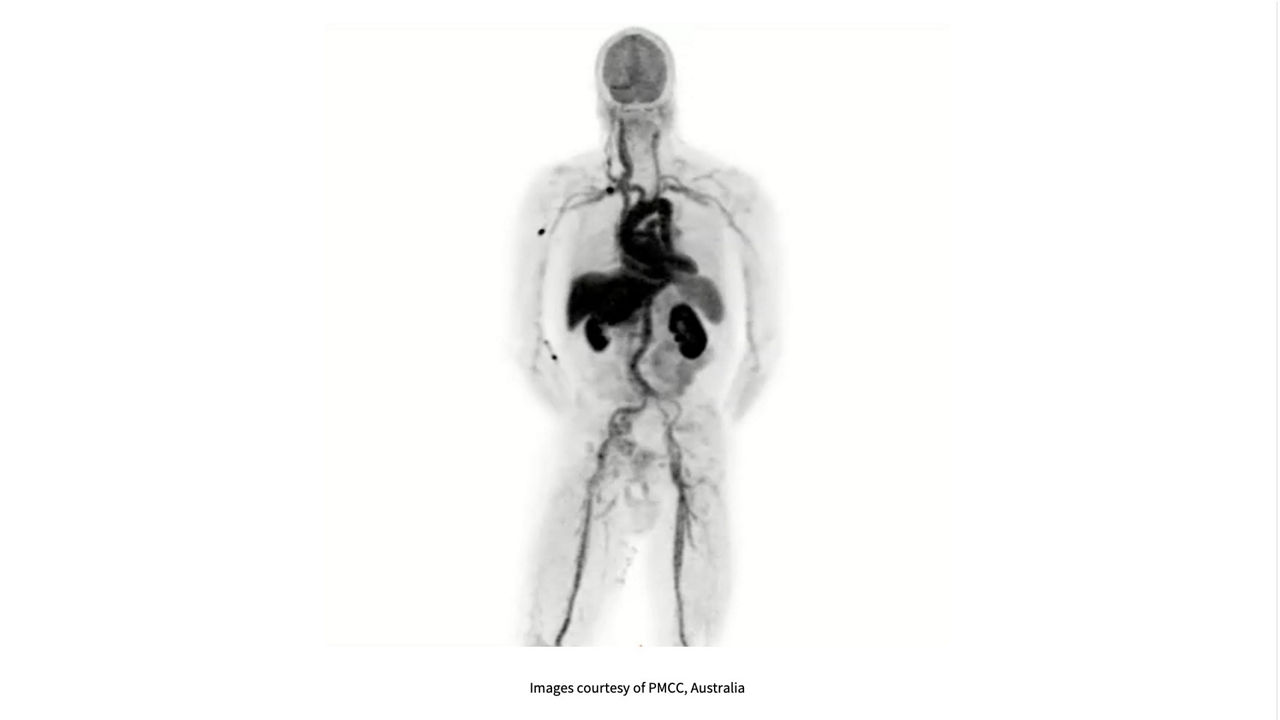

Vertex-to-thigh acquisition in a single bed

Capturing the whole story at once with a 128 cm AFOV opens the door to dynamic and multi-organ acquisitions of virtually all patients, including tall patients¹, generating valuable research data.

Dynamic, simultaneous multi-organ studies from a single holistic scan

Conduct simultaneous multi-organ pharmacokinetic studies that help investigate systemic disease patterns, provide unprecedented physiological insights and accelerate new tracer development.